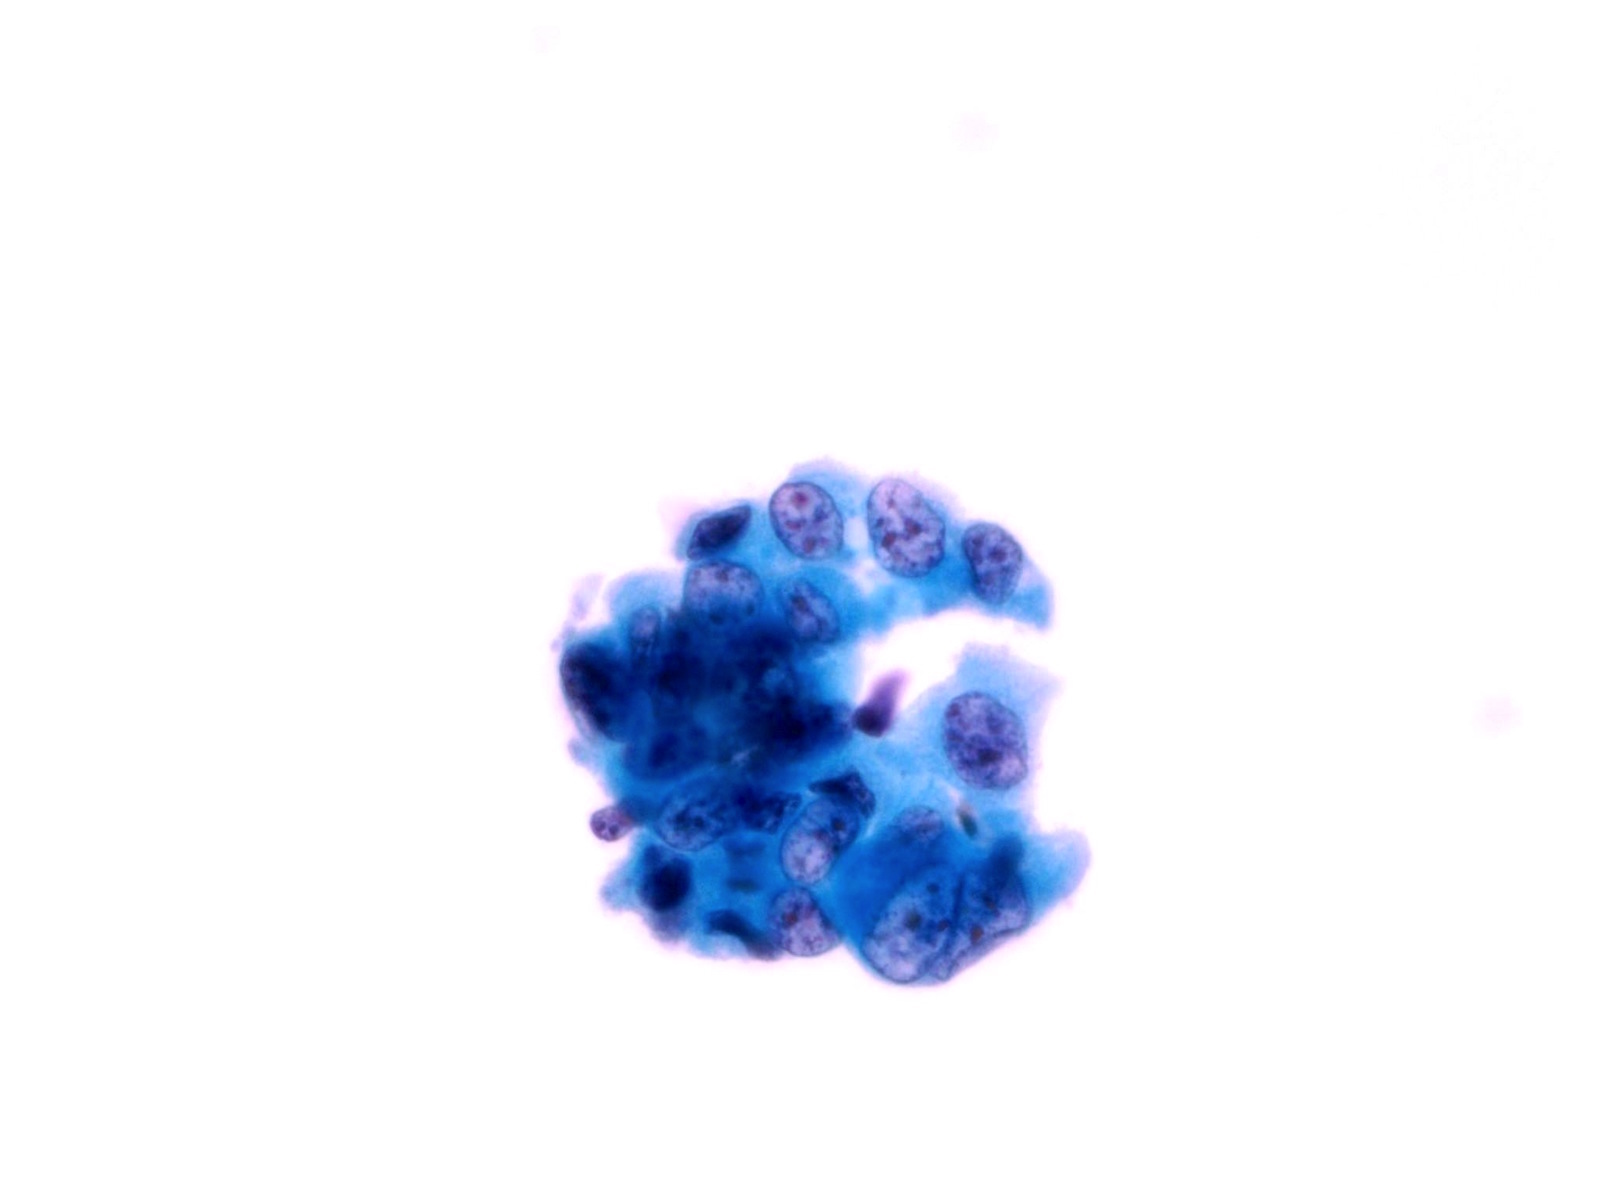

Low Grade Urothelial Neoplasia (LGUN)

- LGUN is a combined cytologic term for low grade papillary urothelial neoplasms, which includes urothelial papilloma, papillary urothelial neoplasm of uncertain malignant potential (PUNLMP) and low grade papillary urothelial carcinoma (LGPUC)

- Definitive diagnosis of LGUN is possible only in the presence of this cytologic criteria (regardless of voided urine or instrumented urine):

- 3 dimensional cellular papillary clusters with fibrovascular cores including capillaries

- Cellular papillary clusters are defined as clusters of cells with nuclear overlapping forming papillae

- The following cytologic features should be categorized as NHGUC:

- 3 dimensional cellular clusters without fibrovascular cores

- Increased numbers of single monotonous (non umbrella) cells

- Cytoplasmic homogeneity

- Nuclear border irregularity

- Increased N/C ratio

- A comment may be added to suggest LGUN in these cases without definitive cytomorphologic features

- Rate of progression is 0% for papillomas, 3.6% for PUNLMP and 5 - 25% for LGPUC (WHO / ISUP classification (2004))